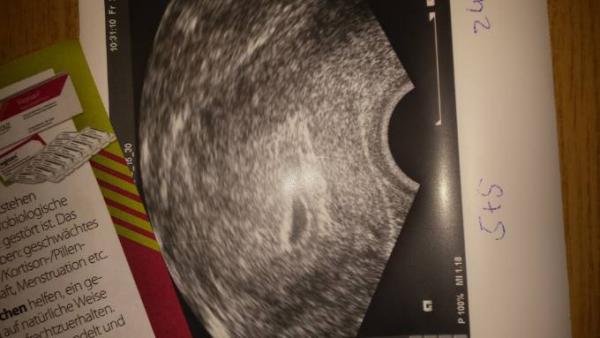

Soooooooo nun kann ich endlich mehr erzählen. Ich bin heute extakt bei 5+5 und alles zeitgerecht entwickelt. FH ist bei 9mm mit einer emryonalen Struktur aber noch keine Herzaktion, die will mein FA dann nächsten Mittwoch sehen